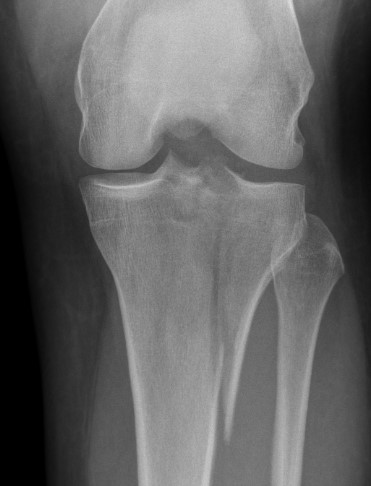

Schatzker Classification

I. Lateral Spilt

- seen in young patient

- lateral meniscus can be incarcerated in fracture

II. Lateral Split Depression

- often seen in young patients with high energy injuries

- vary in severity

III. Lateral Depression

- central depression usually seen in elderly

- have to create lateral cortical window in order to elevate fragment

IV. Medial plateau & intercondylar eminence

- high velocity injury associated with ACL / LCL / CPN injury

- can be low injury / osteoporotic and often unreconstructable

V. Bi-condylar + intact metaphysis

- unstable

- requires ORIF

VI. Bi-condylar + metaphyseal fracture

- fracture separating metaphysis from diaphysis

- highest incidence of vascular injury